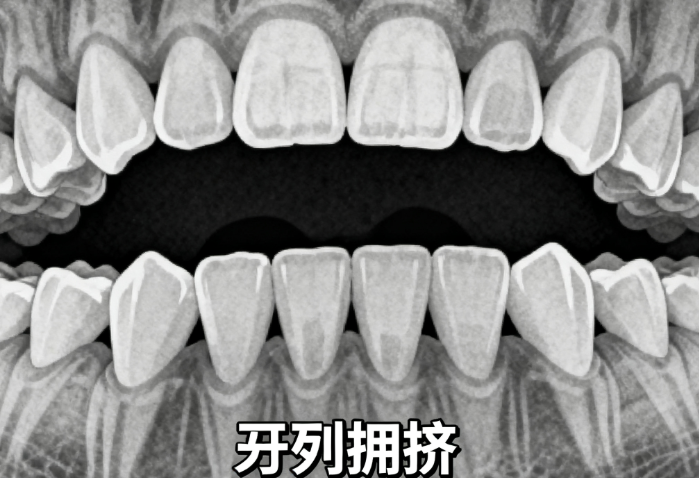

2. 治疗疗效:MRC矫正器可改善上颌前突和下颌后缩问题,能有效排齐牙列,改善深覆合,还能通过训练舌位和吞咽方式促进正常颌骨发育。